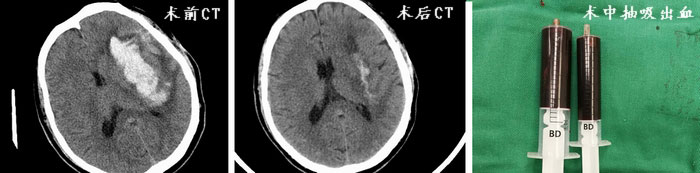

10月12日,我院神经外科通过绿色通道收治了3名危重脑出血患者,入院时患者均有严重的意识及肢体功能障碍。神经外科团队针对患者病情展开讨论,根据患者症状体征及影像学检查,手术指征明确,决定采取颅内血肿穿刺引流。与以往不同的是,术中将使用机器人精准确定病灶穿刺靶点、合理规划并选择路径,从而达到最佳的引流效果。3例不同病变部位颅内血肿在机器人辅助引导下顺利完成穿刺,术后复查头部CT提示颅内出血引流效果满意,三位患者意识及肢体功能得到明显改善,目前正在康复治疗中。